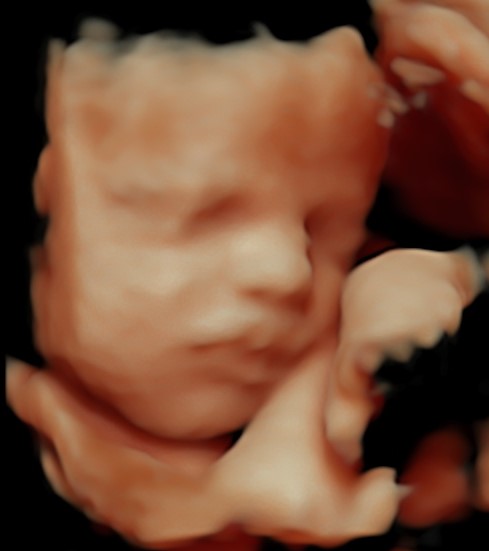

Monmouth County’s First 4D/5D/HD Live Ultrasound Studio

4D/5D/HD Ultrasound Gallery

Gallery